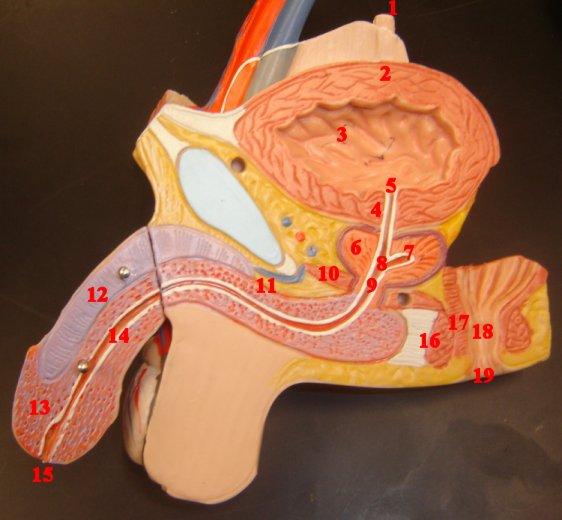

Bulbourethral gland (male)

Corpora cavernosa (pl.) Corpus Cavernosum (s.)

Corpus Spongiosum

Ejaculatory Duct

External urethral orifice (male)

Glans penis

Prepuce (=foreskin)

Prostate gland

Prostatic/spongy urethra (males)

Seminal vesicle

Testis (s.) Testes (pl.)

Ureter

Urethra

Urinary Bladder (male)

Vas deferens (=ductus deferens)